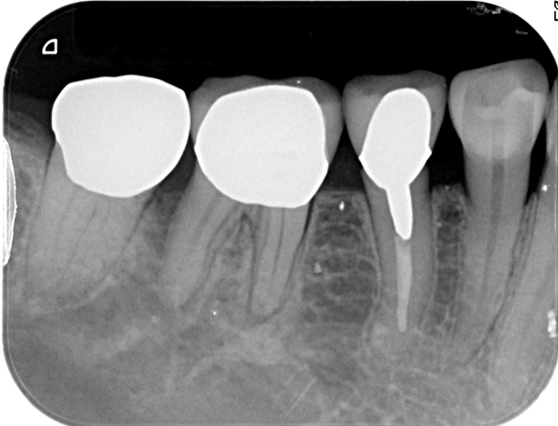

根管治療 症例2

昨年末に治療したばかりのところが歯茎が腫れた

治療前のレントゲンで、腫れているところから原因の確認。

治療部位の神経が死んでしまい、腐敗したことで根っこの先に膿がたまってしまった。

根管治療を提案。